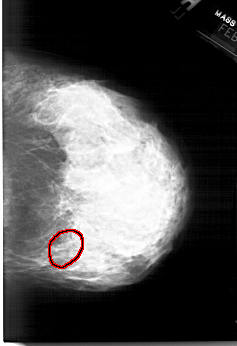

ics_version 1.0 filename A-1564-1 DATE_OF_STUDY 6 2 1996 PATIENT_AGE 43 FILM FILM_TYPE REGULAR DENSITY 4 DATE_DIGITIZED 14 9 1998 DIGITIZER HOWTEK 43.5 SEQUENCE LEFT_CC LINES 6331 PIXELS_PER_LINE 4156 BITS_PER_PIXEL 12 RESOLUTION 43.5 NON_OVERLAY LEFT_MLO LINES 5941 PIXELS_PER_LINE 4321 BITS_PER_PIXEL 12 RESOLUTION 43.5 NON_OVERLAY RIGHT_CC LINES 6226 PIXELS_PER_LINE 4261 BITS_PER_PIXEL 12 RESOLUTION 43.5 OVERLAY RIGHT_MLO LINES 6271 PIXELS_PER_LINE 4501 BITS_PER_PIXEL 12 RESOLUTION 43.5 OVERLAY |

FILE: A_1564_1.RIGHT_CC.OVERLAY TOTAL_ABNORMALITIES 1 ABNORMALITY 1 LESION_TYPE CALCIFICATION TYPE PLEOMORPHIC DISTRIBUTION SEGMENTAL ASSESSMENT 4 SUBTLETY 4 PATHOLOGY BENIGN TOTAL_OUTLINES 1 BOUNDARY |